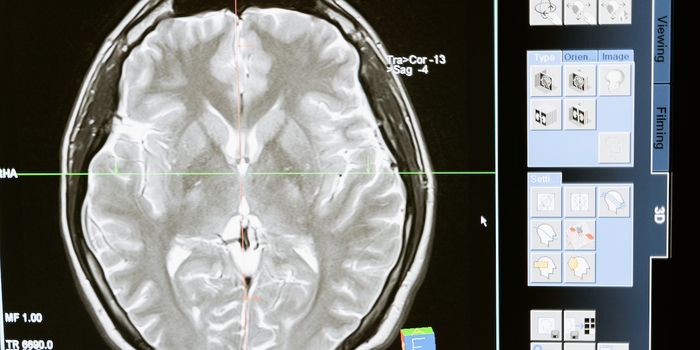

MAY 05, 2020Clinical & Molecular DXImagine a future where we could “see” inside the human brain at stunning high resolution, detecting the earl ...

FEB 08, 2022Clinical & Molecular DXThe human skull is about a quarter of an inch of solid bone, perfectly suited to perform its role as the protecto ...

MAR 15, 2022Clinical & Molecular DXAccording to Alzheimer's Association, one in nine people over 65 are currently living with Alzheimer's dise ...

JUN 28, 2017CancerBrain imaging via MRIs may soon be enhanced with simple sugar instead of conventional metal complexes. A new study found ...

DEC 03, 2020NeuroscienceTo obtain high-resolution images of the brain, researchers usually need to reduce the thickness of the skull or cut into ...